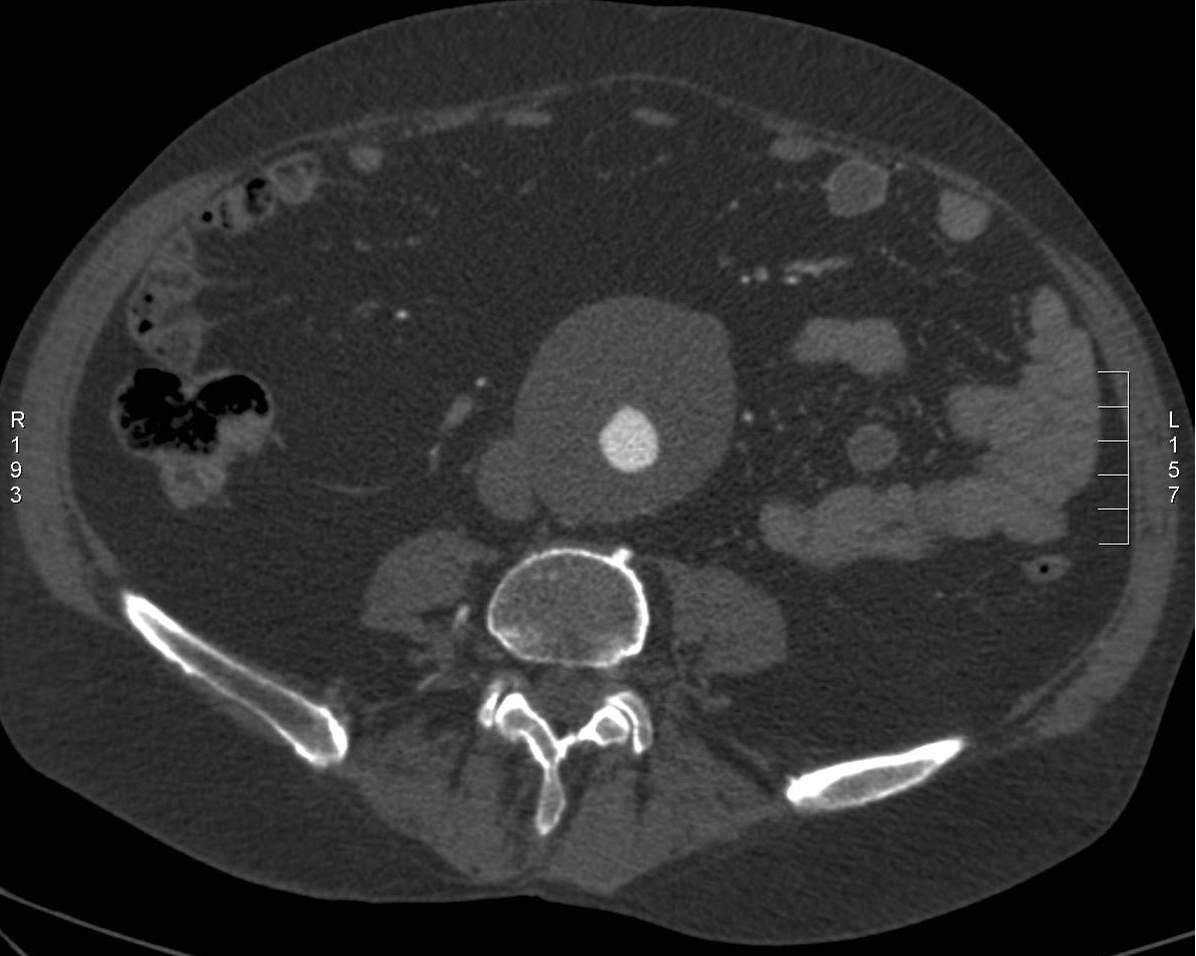

The role of imaging aneurysms, on one hand, is to provide precise measurements about its size, especially about its greatest diameter, on the other hand, to follow-up the patients. An aortic aneurysm with a diameter above 6 cm is considered at a high risk for a rupture and requires interventional procedure. Dilatations over 5 cm require a close monitoring to be able to detect any further increase in size in time. Aneurysms of a size smaller than 5 cm require imaging follow-up at every 6 months or once a year if their size does not change. Beside the precise measurements, the role of imaging is also to characterize the appearance of the lesion in order to select ones that require surgical reconstruction and ones that are suitable for endovascular intervention. The anatomic characteristics that should be assessed at each imaging examination are: the location of the proximal and distal neck of the aneurysm, the relation of the origin of the side branches, wall thickness, the thickness of the mural thrombus and finally to detect signs in the perivascular tissues that are suggestive of an impending rupture.

Ultrasound examination is a reliable screening tool and is also useful for patient follow-up. However, the reproducibility of the diameter measurements of an irregularly shaped vessel is considered limited. Contrast enhanced US can increase the diagnostic sensitivity for such hardly depictable lesions. CT and MRI are able to assess well aneurysms regardless of their location and size. They provide the highest visibility for primary diagnostics and planning of surgical interventions. Intrathoracic and intracranial aneurysms can only be followed up with these techniques since US examination has limited ability in these regions. In case of scheduled examinations MRI is the preferred method, if available, since it does not come with harmful radiation which would accumulate in a constantly controlled patient. In cases when rupture is suspected CT is the method of choice due to its higher availability in emergency and shorter examination time

Image

A non-ruptured (stable) aneurysm with an extended mural thrombus

Ruptured aneurysm with retroperitoneal hematoma

Fig. 24., 25.: Abdominal aorta aneurysm, CT angiography